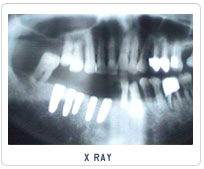

Implant Cases

Case 1   Case 2   Case 3   Case 4   Case 5   Case 6   Case 7   Case 8

Pictures Before And After Dental Implant India,Dental Implant Methods India,Types Of Materials Dental Implant Chennai India,X-ray Dental Surgery Goa India,Replacement Of Damaged Teeth Cochin India,Views Of Dental Treatment Procedure Delhi India,Dental Equipments Hyderabad India